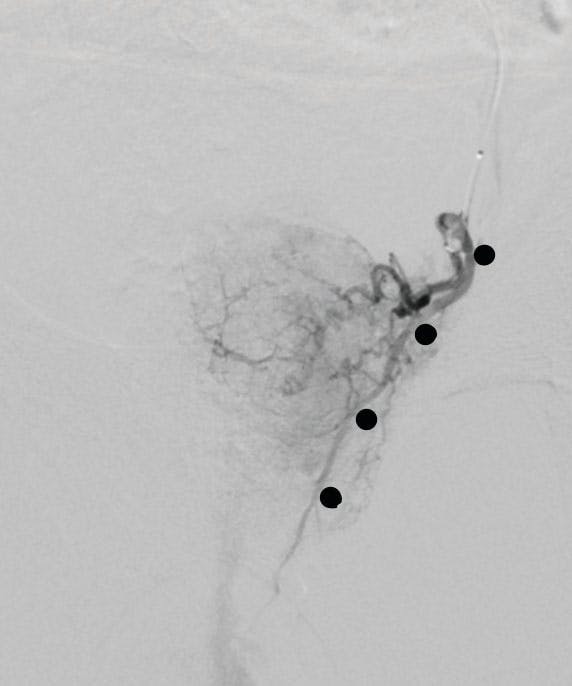

Case Snapshot From Dr. Misono

A man in his early 70s presented with a history of hypertension, hyperlipidemia, diabetes, atherosclerosis, and BPH. He previously underwent transurethral resection of the prostate, which initially helped but is no longer effective. Currently, he urinates up to 30 times daily, about half urgently and often resulting in incontinence. The patient experiences nocturia as well as recurrent episodes of hematuria, sometimes passing up to a cup of bloody urine with clots.

Figure 1. The prostate artery arising from the internal pudendal.

Figure 2. The rectal branch just proximal to the prostate artery—must cannulate past this branch.